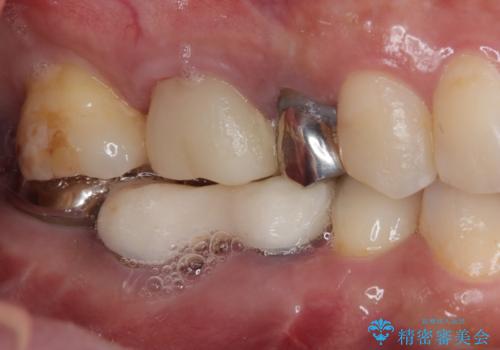

放置していたむし歯 抜歯即時埋入インプラントによる補綴治療

- むし歯を放置したままで、インプラント治療を希望して来院された患者様です。

左右ともにインプラントが必要な状態でした。

左下小臼歯は根管治療で対応する予定でしたが、診断のために歯肉を開いたところ頬側に垂直破折が認められたため、抜歯即時埋入インプラントによる補綴治療を選択することとしました。

右下は大臼歯部の歯は抜歯即時埋入インプラントにて、手前の歯は保存して補綴治療を行うこととしました。

インプラント埋入時に十分な安定値を得ることができたため、速やかに仮歯を装着し、最小限の通院回数で治療を終えることができました。